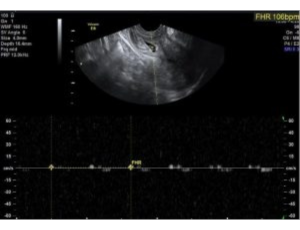

This female unfortunately conceived with a pregnancy in the lower part of the womb or cervix, following fresh transfer in an IVF cycle. This is a cervical ectopic pregnancy, a very rare presentation, but nevertheless, a life-threatening condition.

Dr Kriti Agarwal diagnosed the condition early through TVS and managed it successfully with an injection called methotrexate, which dissolved the pregnancy completely without the need for surgery. She monitored the patient through ultrasound and serial blood hormonal tests only.

On follow-up, the patient was clinically stable, and follow-up ultrasound and pregnancy hormone tests were negative for pregnancy.